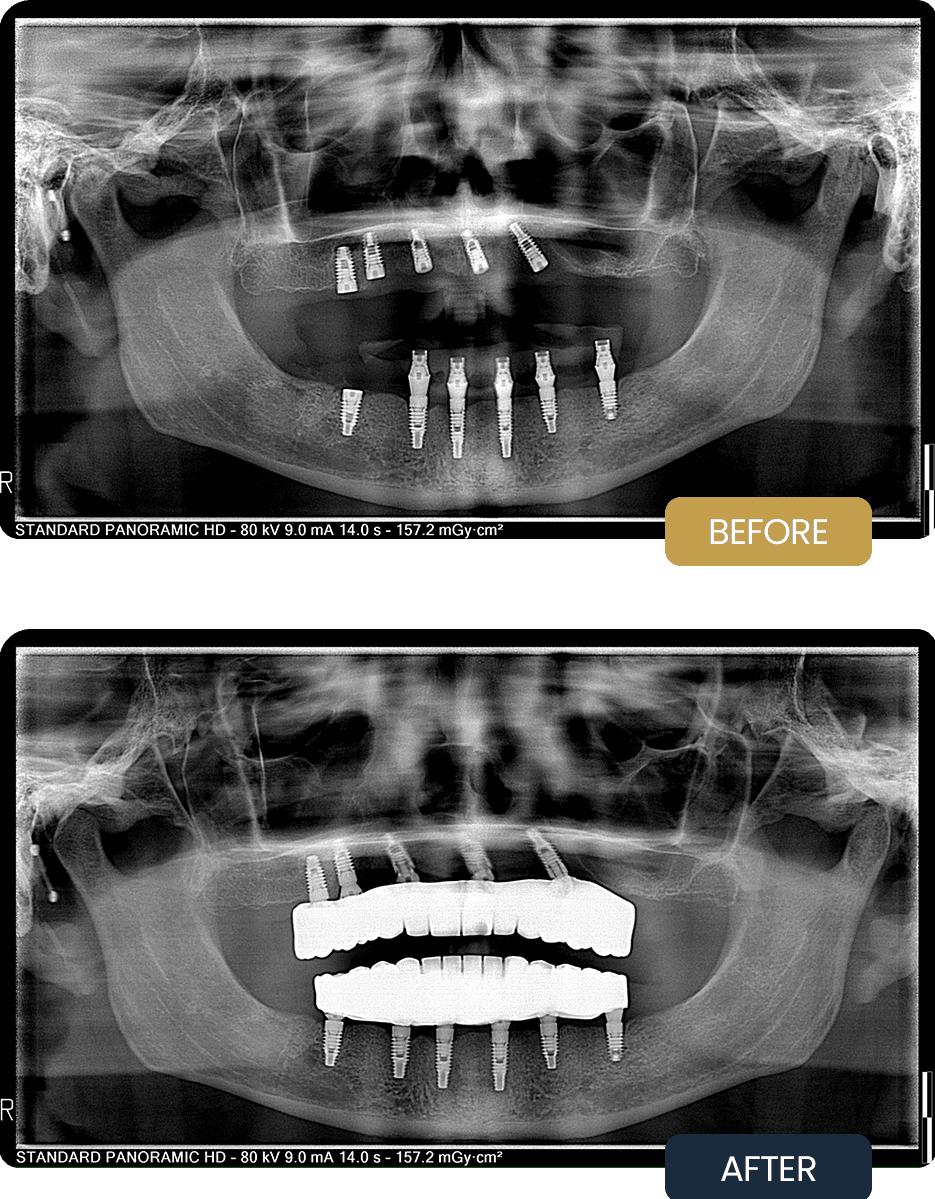

A full arch implant rehabilitation was planned for both jaws using a combined All on 5 and All on 6 approach, tailored to the anatomical conditions and bone availability of each arch. Five implants were placed in the upper jaw to achieve stable anterior posterior support while respecting anatomical structures and available bone volume. Six implants were placed in the lower jaw to enhance load distribution and provide increased long term stability.

Implant positioning was carefully planned to optimise bone utilisation and ensure balanced force transmission across both arches. Posterior implants were placed with controlled angulation where required to maximise support and minimise stress concentrations.

The pre treatment panoramic radiograph illustrates compromised dentition and bone conditions, highlighting the need for a complete implant supported rehabilitation to restore long term oral function and stability.

Post treatment panoramic imaging confirmed successful integration of all implants in both arches, with well positioned All on 5 and All on 6 supported restorations. Implant alignment and distribution provided stable support for the final prostheses.